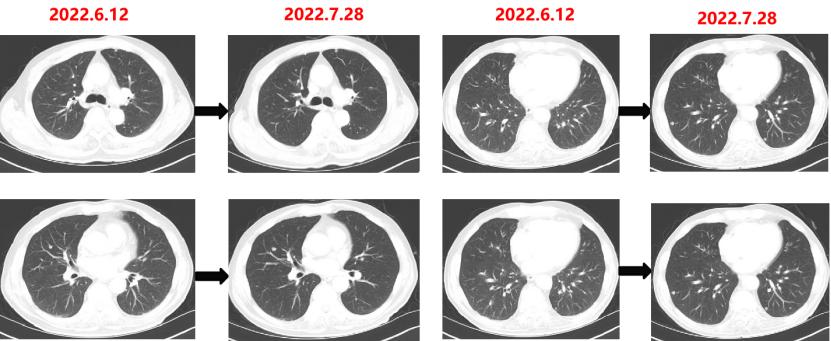

疗效对比:

给予贝伐珠单抗联合TAS-102治疗期间复查CT评估SD,胃肠道反应不重,骨髓抑制Ⅰ度,耐受性尚可。